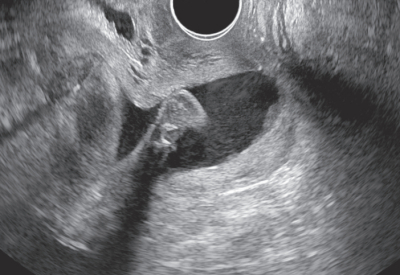

身長154cm、体重56kg(非妊時52kg)。体温37.1℃。脈拍88/分、整。血圧126/74mmHg。呼吸数18/分。腹部は妊娠子宮で膨隆し、柔らかい。腟鏡診で分泌物は粘液性で少量の血液が混じっている。経腹超音波検査では正常脈で足位の児を認める。経腟超音波画像を別に示す。